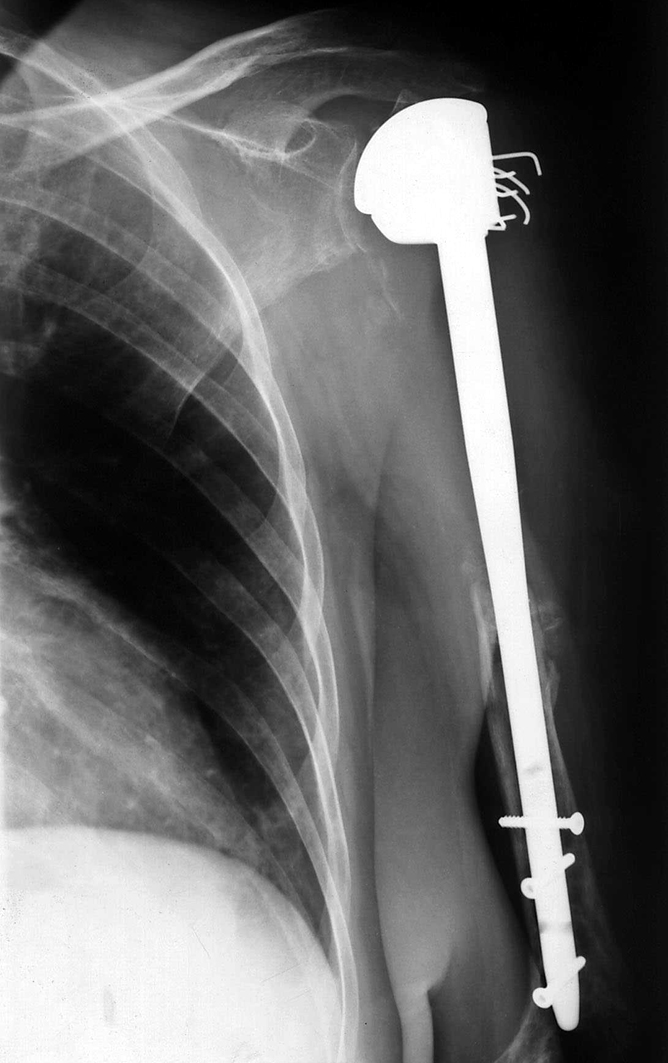

"Aufgrund der fehlenden Durchblutung war ein Teil des Oberarmknochens abgestorben", stellte Chefarzt Schmidt bei der ersten Untersuchung fest. Zur Vermeidung einer Armamputation ließ Schmidt von einer Berliner Firma ein Implantat aus Titan anfertigen, das den abgestorbenen Knochen ersetzt. "Eine Maßanfertigung", so der Bucher Chefarzt.

Zunächst setzte das OP-Team unter der Leitung von Oberarzt Dr. med. Jan Kühling die neue Hüfte ein. Danach wurde das abgestorbene Knochenstück des Oberarms entfernt und durch eine Knochenprothese aus Titan ersetzt. Diese wurde am Schulterblatt und am intakten Teil des Knochens oberhalb des Ellenbogens verankert.